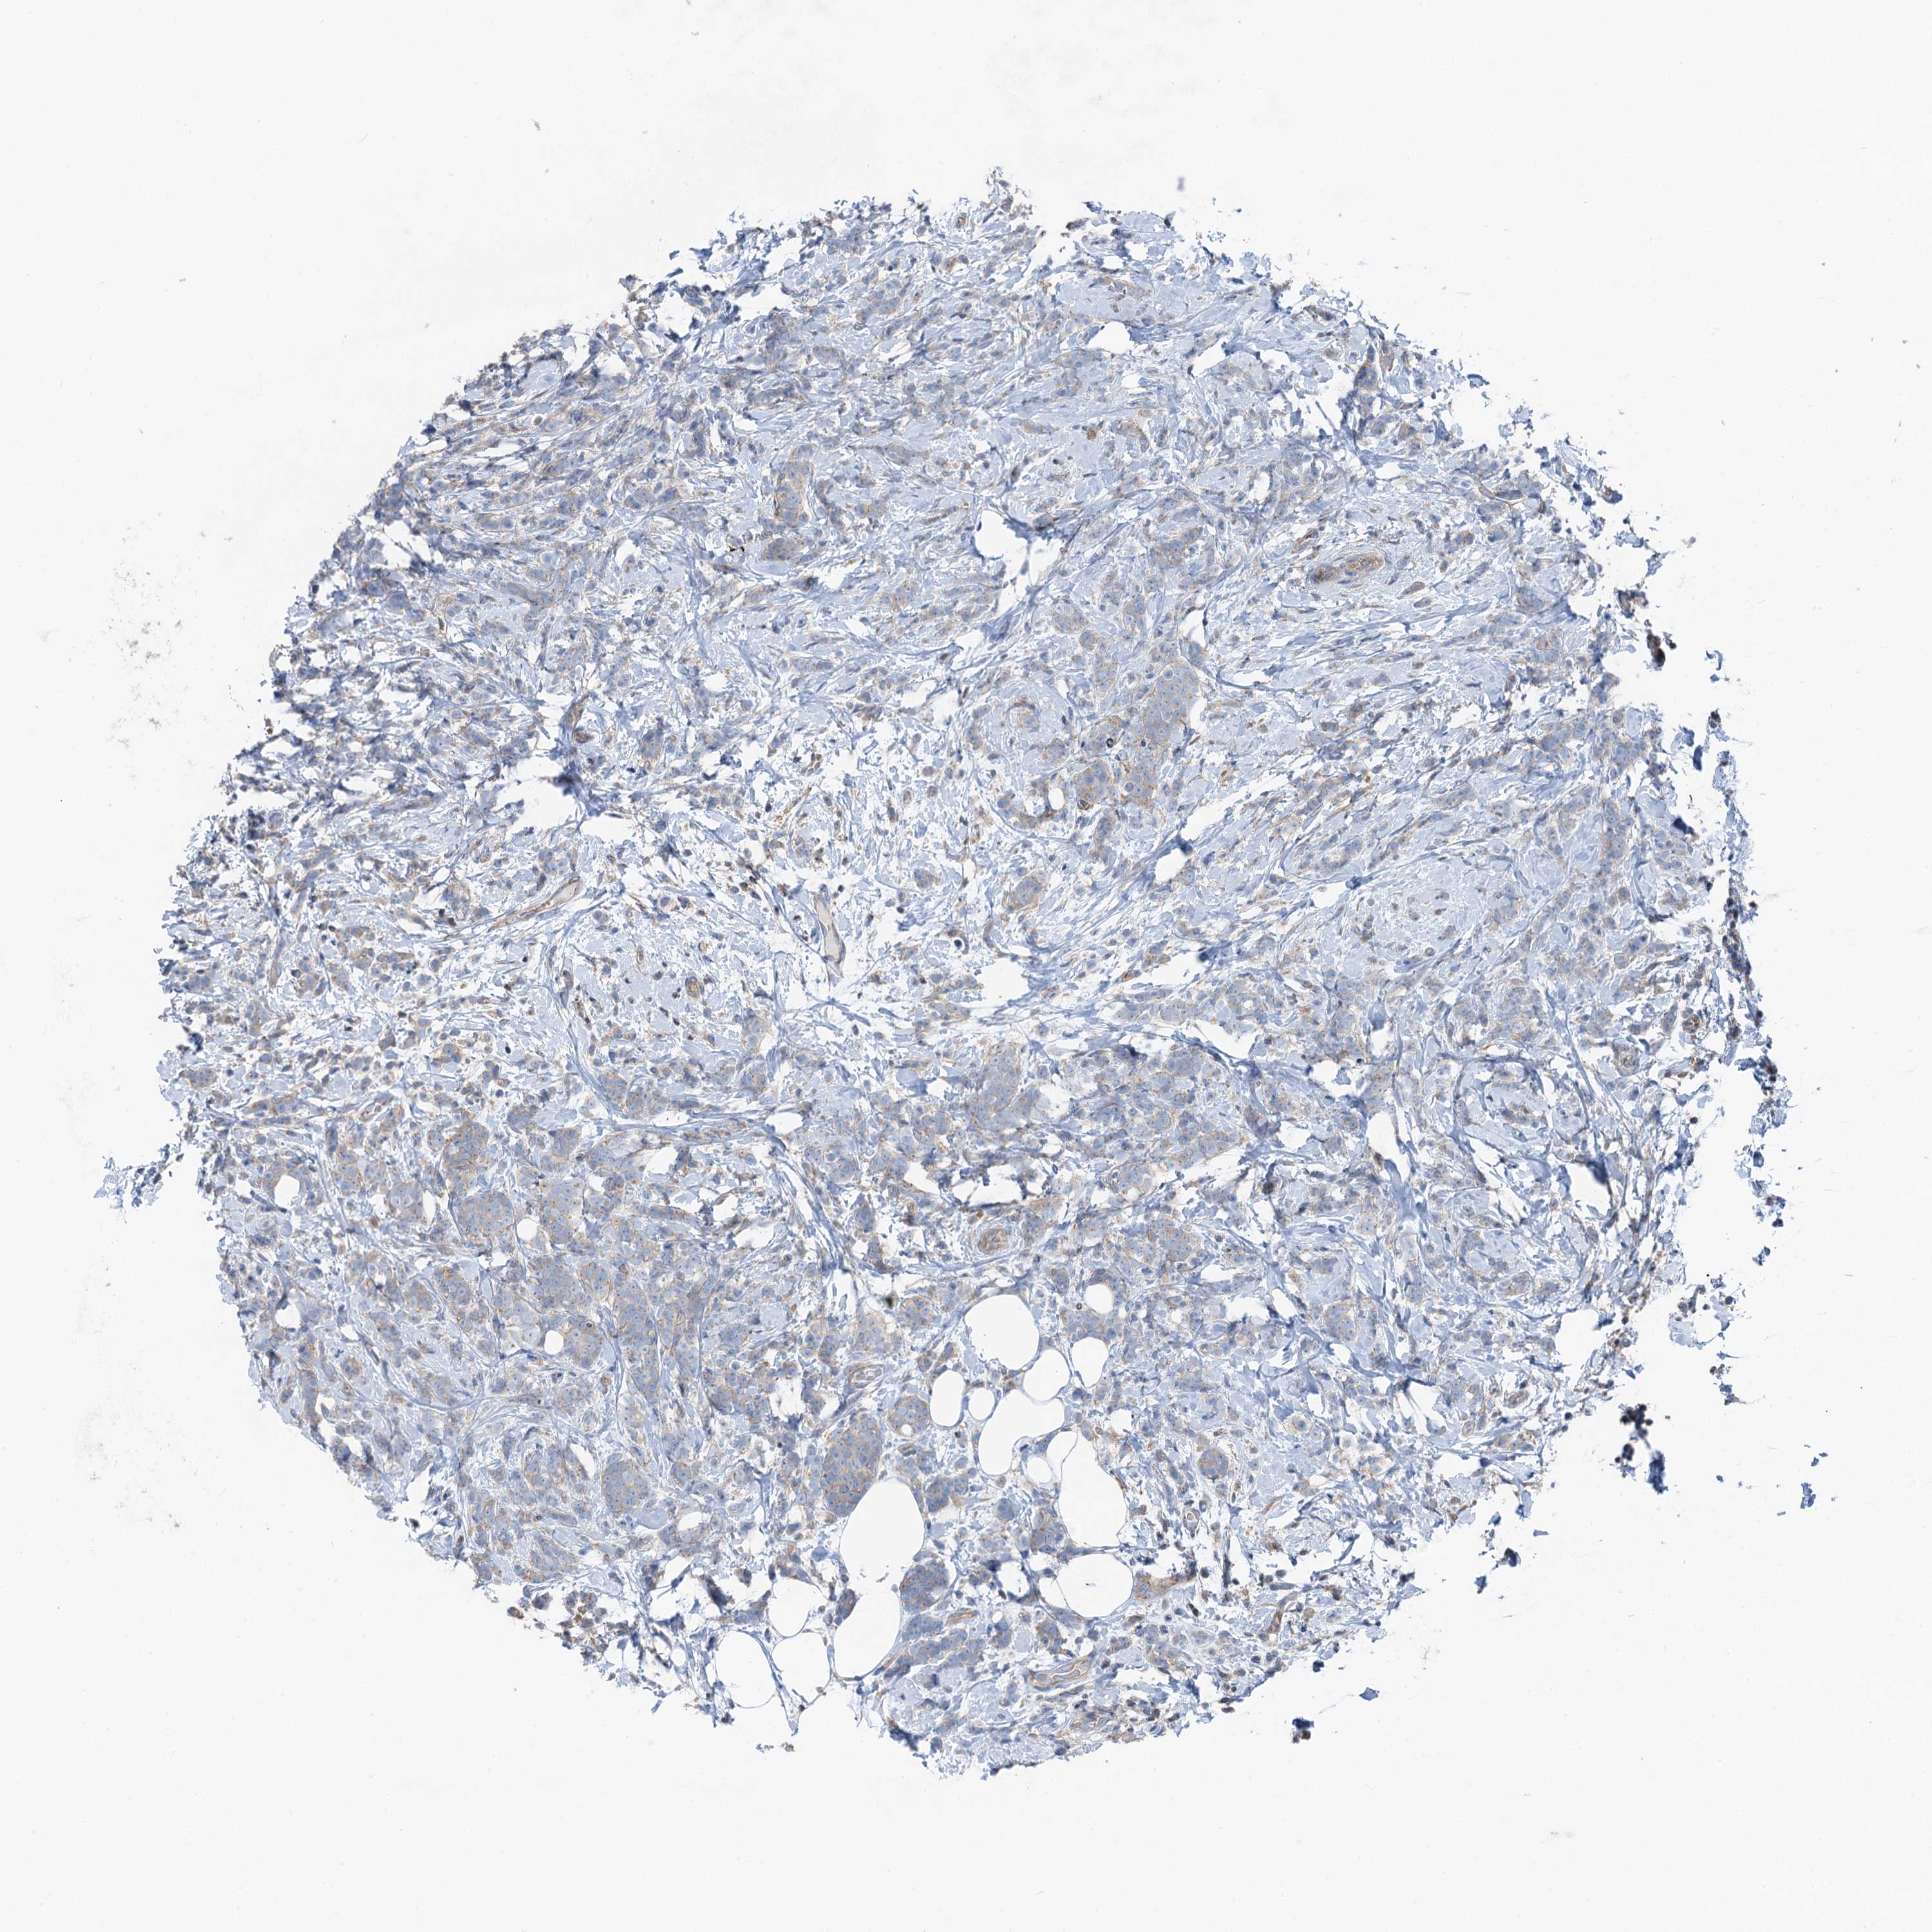

CANCER BREAST CANCER Show tissue menu

BRCA TCGA BRCA VALIDATION PROTEIN EXPRESSION